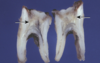

periapical granuloma

periapical granuloma

periapical granuloma

periapical granuloma